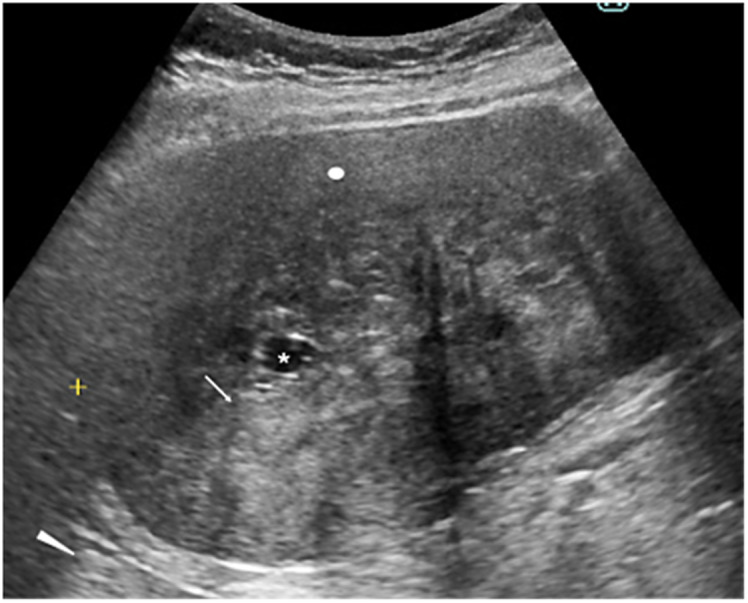

Case presentation: An 80-year-old woman was referred to our hospital due to the detection of an abdominal mass on ultrasound (US). CT showed a well-demarcated oval mass, 11 cm in size, with a central low-density area. US showed high internal echoes and enhanced posterior echoes. Magnetic resonance imaging (MRI) showed the low-density area on CT to be hypo-intense on T1-weighted images and hyper-intense on T2-weighted images. MRI further showed the central part of the tumor to be hyper-intense both on diffusion-weighted images and apparent diffusion coefficient images. Under the tentative diagnosis of a gastrointestinal stromal tumor with central necrosis, the patient underwent tumor resection, revealing the tumor to be a jejunal submucosal tumor. Pathological study showed collagen fibers with heterogeneous density and sparse proliferation of spindle cells. The center of the tumor had marked edema in addition to sparse collagen fibers. Immunostaining showed that the atypical cells were diffusely positive for β catenin and negative for S100 protein, desmin, and DOG1, leading to the diagnosis of desmoid tumor (DT).